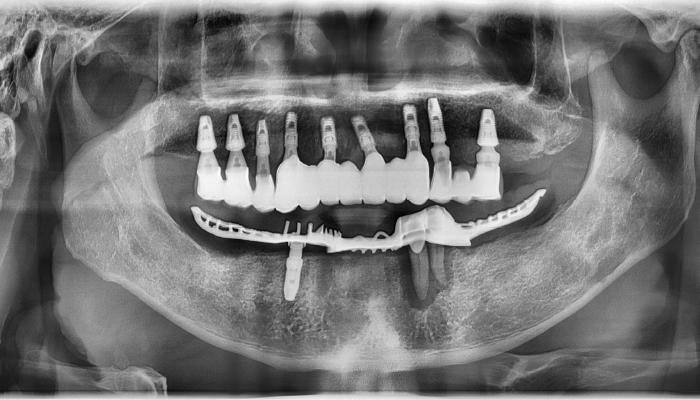

뼈이식 임플란트 전후 사례

식립후

보철물 연결

임플란트 상태 확인 후 상부 구조물 연결하고 본을 떠 보철물을 제작합니다.